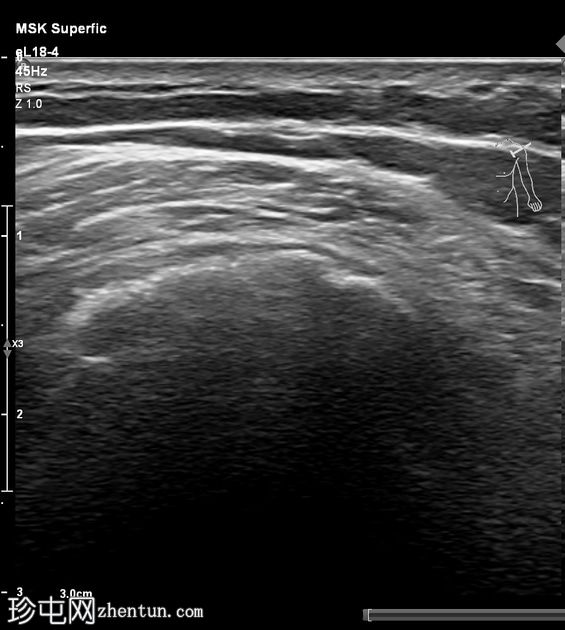

超声

横断面

侧位面

冈上肌腱可见弧形声反射,边缘呈分叶状,远端声影逐渐加重,符合钙化表现。

典型的钙化性肌腱炎超声和X线表现。肩袖是最常受累的部位,冈上肌腱受累的病例占80%,本例亦是如此。